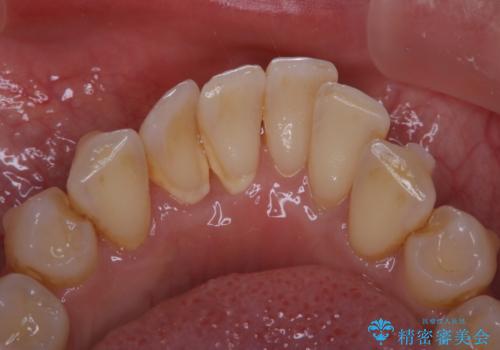

インビザライン中の歯石取り PMTC

- インビザライン治療中のお口の中の汚れが気になるとのことでした。PMTC30分コースを行いました。

インビザライン矯正治療中は、ご自身の歯にアタッチメントという突起物(効率的に歯の移動を行うため)をつけます。そのため、通常時よりも歯石やステインが付きやすい状態になることがあります。

インビザラインは透明なマウスピースなので、ご自身の歯に歯石やステインなどが付着していると、見た目に影響してしまうことがあります。

矯正治療中の虫歯・歯周病・口臭予防としても、定期的にPMTCを行うことが大切です。